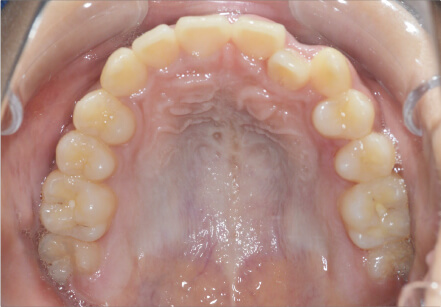

叢生の症例

17歳

/

女性

相談内容

カウンセリング・診断結果

治療内容・方法

全額アライナー矯正

術後の経過・現在の様子

クリアライナー使用

治療のリスク

痛み・歯根吸収・歯肉退縮・虫歯・後戻り

費用・治療期間

715,000円、2年10ヶ月

トレーニングなど